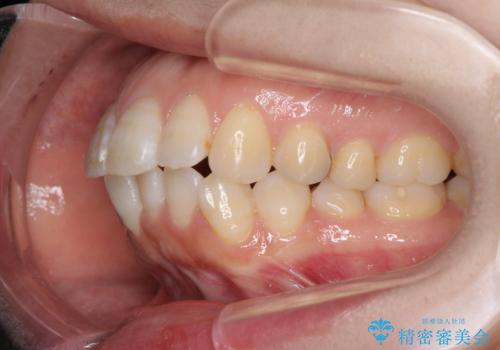

積極的に前歯を牽引したことで、口元の閉じにくさは顕著に改善され、横顔のシルエットが大幅に変化しました。

- 2年10ヶ月

- 10-30回